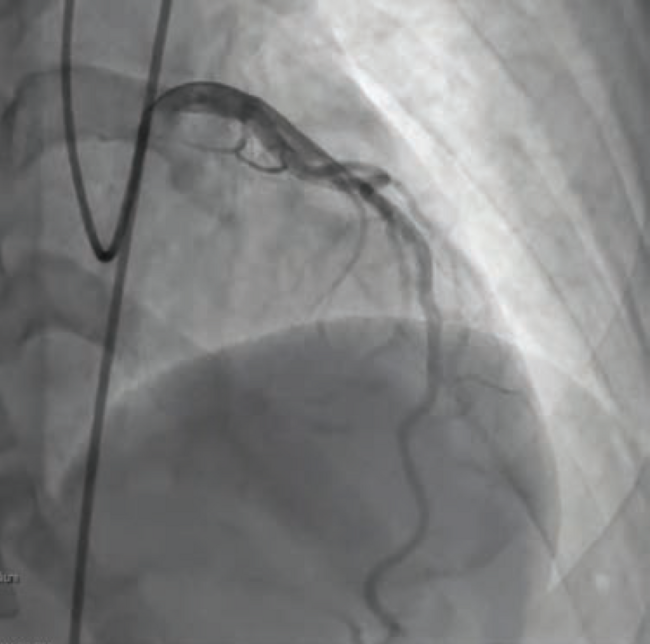

For our patient’s CFT analysis, a coronary angiogram was performed and regarding epicardial disease, demonstrated unchanged results from the previous angiogram (Figure 1). Next, we confirmed a negative invasive functional test for CMD (Figure 2). However, because the patient developed chest pain and demonstrated ST changes on electrocardiogram during ACh provocative testing, without epicardial spasm, her assessment was positive for microvascular vasospastic angina.

Once in the cath lab, the team of nurses and technologists worked swiftly alongside Dr. Case to first establish safe femoral access (ultrasound guidance and micropuncture technique) given the patient’s hemodynamic instability. Next, while promptly inserting a temporary venous pacemaker to address the patient’s complete heart block, the first episode of ventricular fibrillation occurred, and the first shock was successfully delivered. The team then placed an intra-aortic balloon pump (IABP) for cardiogenic shock management in the setting of right ventricular (RV) infarct. The operator used a 5 Fr Judkins left (JL)4 catheter to perform left coronary angiography and a 6 French hockey stick guide catheter for right coronary angiography. The patient was noted to have instent thrombosis (Figure 1), requiring mechanical aspiration thrombectomy (Penumbra). During the intervention, the patient experienced recurrent ventricular fibrillation. The cath lab team worked in unison to successfully deliver 19 shocks throughout the procedure, while administering several intravenous medications, including amiodarone, lidocaine, magnesium, bicarb, and Levophed (norepinephrine bitartrate), per the operator’s orders. Despite the critical arrhythmias and several interventions required to stabilize the patient, the team achieved a remarkable 49-minute door to balloon time in this case.